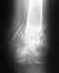

Мне 31 год.28.01 09. получил закрытый перелом большеберцовой кости со смещением.3.02.09 проведен остеосинтез большеберцовой кости блокирующим стержнем.При выписке получил письменную рекомендацию-динамизировать через 4-5недель. Участковый травматолог, уходя в отпуск, на вопрос о том, что такое динамизация бросил: винтик какой-то должны выкрутить. Все!!! какой, когда, зачем-непонятно. На снимках от 27.04. отчетливо видно место перелома.Рекомендовали кальций и мумие в теч. 10 дней( всего?!). Я пил 2 месяца.РЕзультат нулевой. Сегодняшние снимки прокомментированы так: отчетливо просматривается место перелома, явно выраженный остеопороз. Сейчас хожу с одним костылем около двух недель,при длительной ходьбе появляются боли в стопе, очень редко -в месте перелома.Больше ничего не беспокоит. Могу пройти немного по квартире без костылей. Вопрос: нужна ли мне динамизация и что делать с остеопарозом? Насколько я понял из прочитанных в интернете статей и обсуждений, остеопороз невозможно выявить по снимкам -нужен анализ плотности костной ткани.Зачем же так безапелляционно заявлять о его наличии?